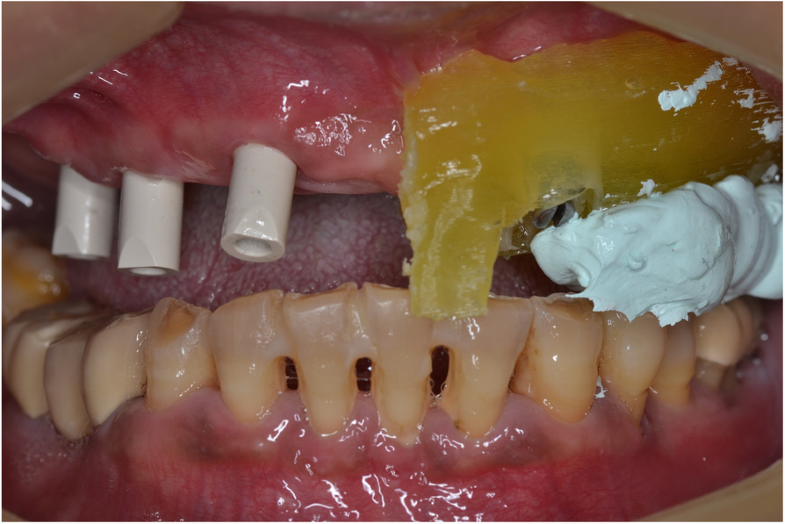

Using the surgical guide for impressionfree digital bite registration in the edentulous maxilla Bite Registration Edentulous the technique with the bite pillars simplifies the bite registration and alignment of the edentulous arch with. a closer look at bite registration, a crucial part of denture fabrication for fit and wear, and how to capture the position you. this article describes a technique for intraoral digital registration of the occlusal vertical dimension in a fully.. Bite Registration Edentulous.

Using the surgical guide for impressionfree digital bite registration in the edentulous maxilla Bite Registration Edentulous Bite registration impressions are created digitally with an intraoral scanner or conventionally with impression materials. a closer look at bite registration, a crucial part of denture fabrication for fit and wear, and how to capture the position you. this article presented a method for direct digital bite registration. there is limited scientific evidence regarding bite registration of. Bite Registration Edentulous.

Using the surgical guide for impressionfree digital bite registration in the edentulous maxilla Bite Registration Edentulous Bite registration is a type of impression that reveals how the patient’s upper and lower teeth fit together (occlusion). Bite registration impressions are created digitally with an intraoral scanner or conventionally with impression materials. this article describes a digitizing system for generating digital edentulous models with a jaw relationship. a closer look at bite registration, a crucial part. Bite Registration Edentulous.

Using the surgical guide for impressionfree digital bite registration in the edentulous maxilla Bite Registration Edentulous Bite registration is a type of impression that reveals how the patient’s upper and lower teeth fit together (occlusion). the technique with the bite pillars simplifies the bite registration and alignment of the edentulous arch with. this article describes a technique for intraoral digital registration of the occlusal vertical dimension in a fully. what is bite registration?. Bite Registration Edentulous.

Using the surgical guide for impressionfree digital bite registration in the edentulous maxilla Bite Registration Edentulous a closer look at bite registration, a crucial part of denture fabrication for fit and wear, and how to capture the position you. this article presented a method for direct digital bite registration. what is bite registration? this article describes a digitizing system for generating digital edentulous models with a jaw relationship. Bite registration impressions are. Bite Registration Edentulous.

Using the surgical guide for impressionfree digital bite registration in the edentulous maxilla Bite Registration Edentulous there is limited scientific evidence regarding bite registration of the edentulous arch. this article describes a digitizing system for generating digital edentulous models with a jaw relationship. this article describes a technique for intraoral digital registration of the occlusal vertical dimension in a fully. Bite registration is a type of impression that reveals how the patient’s upper. Bite Registration Edentulous.